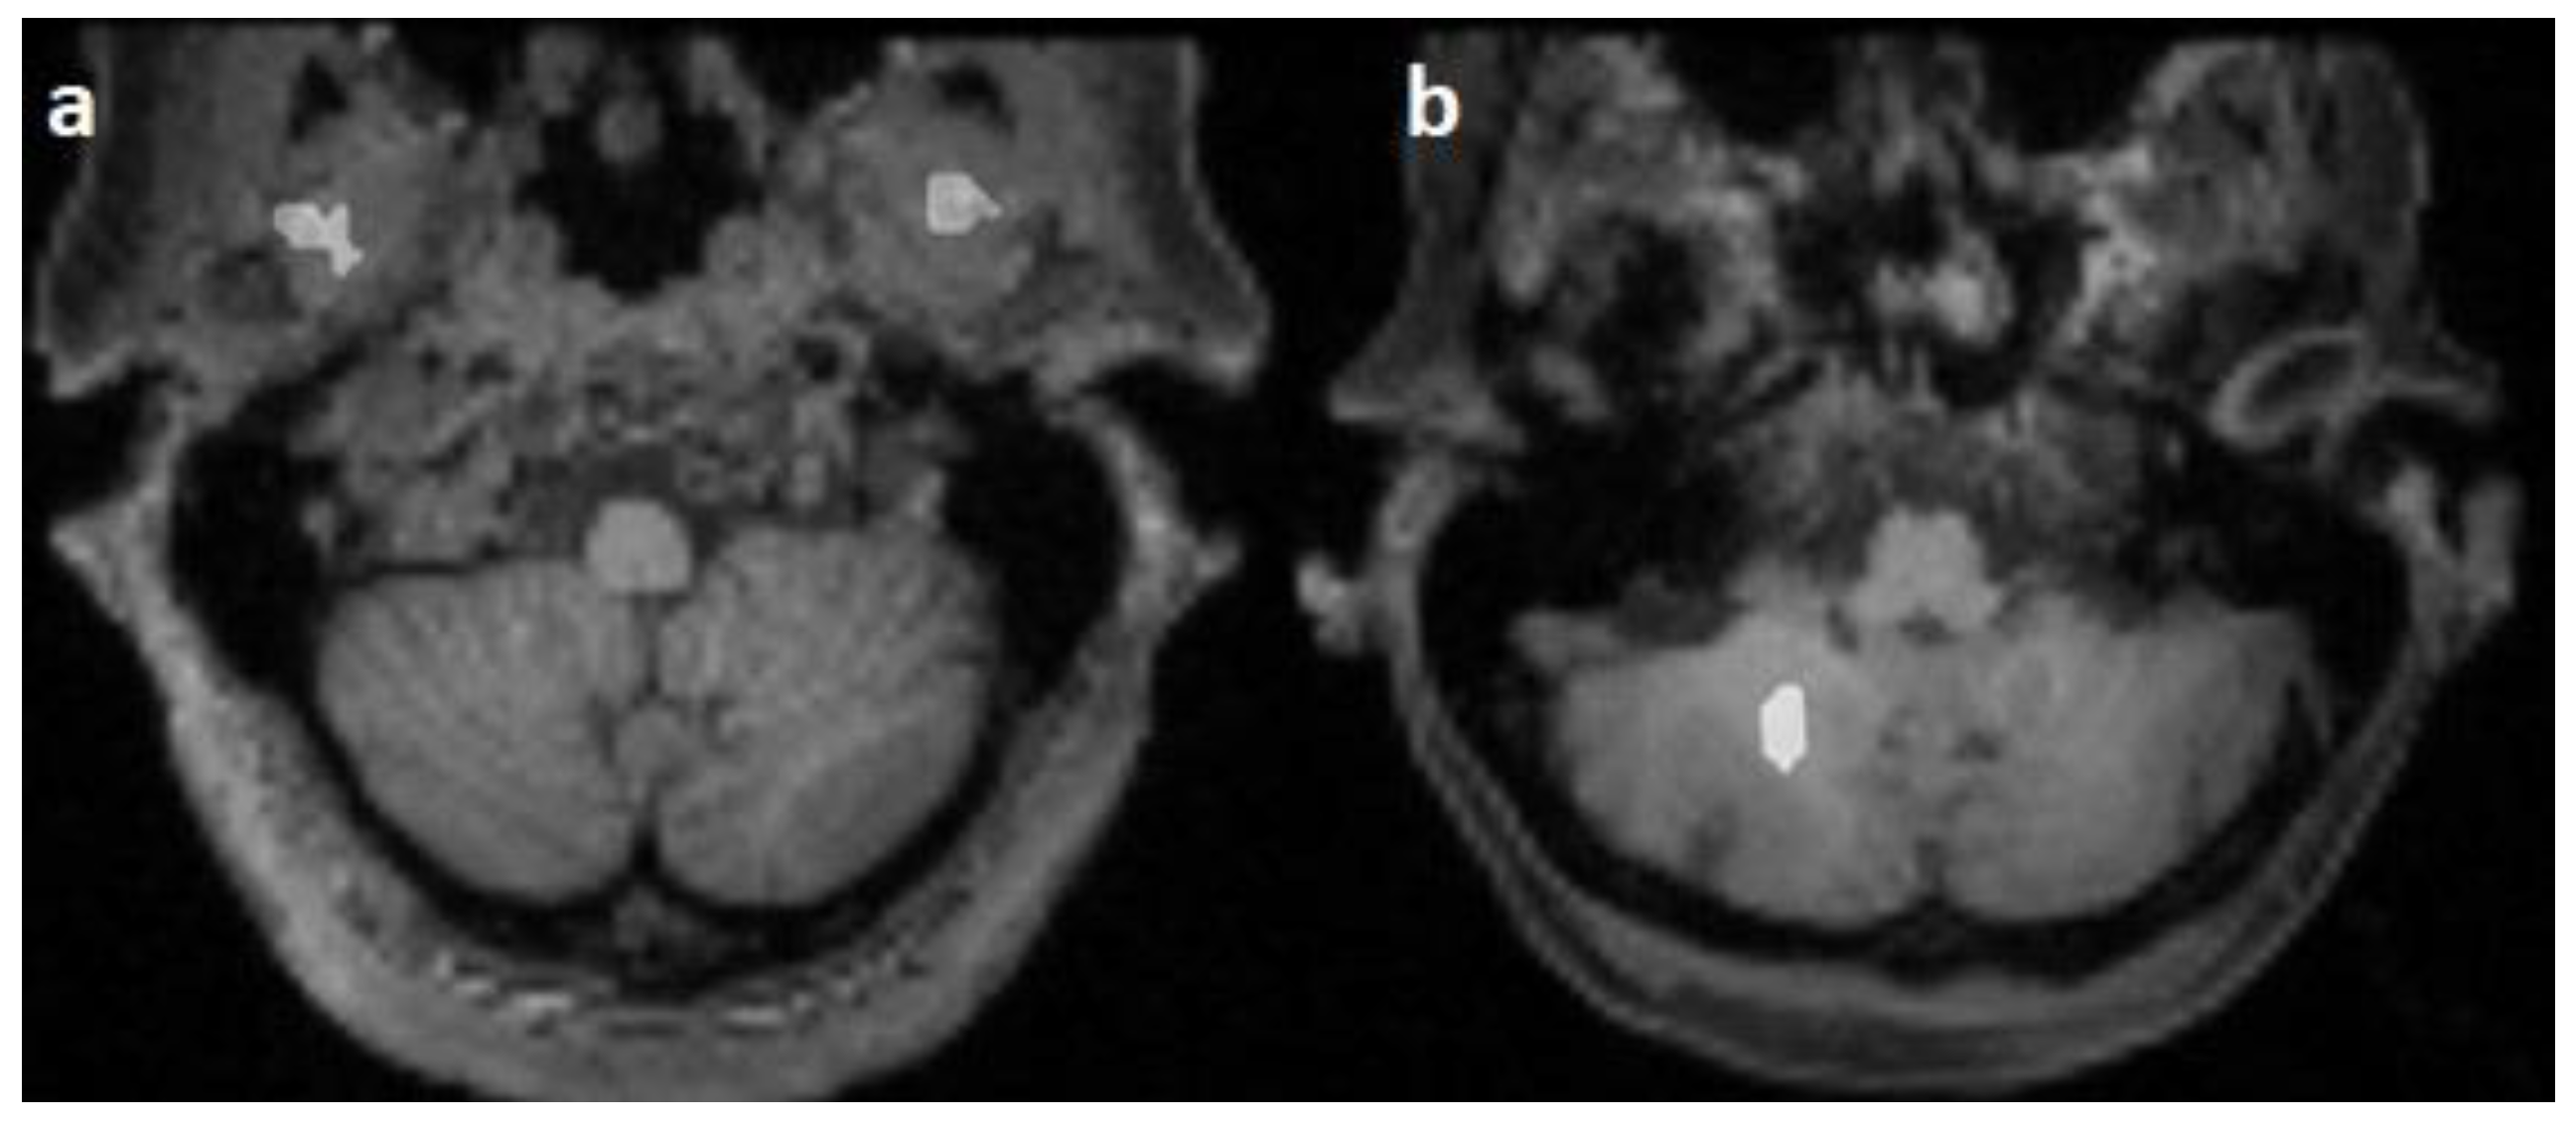

False predicted areas were observed in 23/100 cases (23%) of 3 datasets, with 15 subjects (15/25, 60%) in the Emotion regulation dataset, 7 subjects (7/10, 70%) in the interTVA dataset, and 1 (1/15, 6.66%) subject in the Forrest Gump dataset being affected. According to the course of the pontocerebellar tract, the right hemisphere of the cerebellum was the most common (12/23, 52.17%) falsely segmented area. False prediction in the region parotideomasseterica was observed in 7 cases (7/23, 30.43%), in the pterygoid muscles in 3 cases (3/23, 13.04%), and in the constrictor muscles of the pharynx in 2 cases (2/23, 8.69%) (Figure 4). However, the course of the corticospinal tract was correctly predicted in 19 cases (19/23, 82.60%). In 4 cases, the predicted pathway originated from the centrum semiovale. The number of subjects with falsely segmented areas differed significantly between the groups acquired with Phillips (n = 1) and Siemens scanners (n = 22) (p < 0.001).

Figure 4.

Falsely segmented areas (white) on horizontal T1-weighted images: mm. pterygoidei (a) and cerebellum (b).